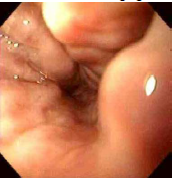

Endoscopic views of esophageal varices are shown below,

with dilated veins bulging into the lower esophageal lumen.